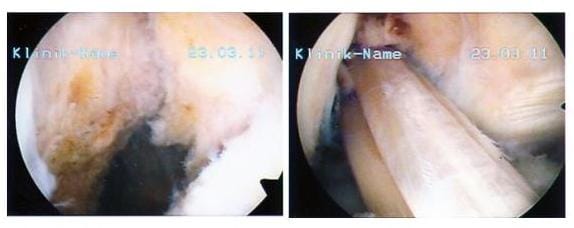

Bild links zeigt das fehlende vordere Kreuzband rechts ist es durch körpereigenes Sehnengewebe ersetzt worden

Arthroskopisch assistierter Ersatz des vorderen Kreuzbandes (VKB): Das linke Bild zeigt das fehlende VKB, rechts ist es durch körpereigenes Sehnengewebe ersetzt worden. (Bilder: Orthopädie)